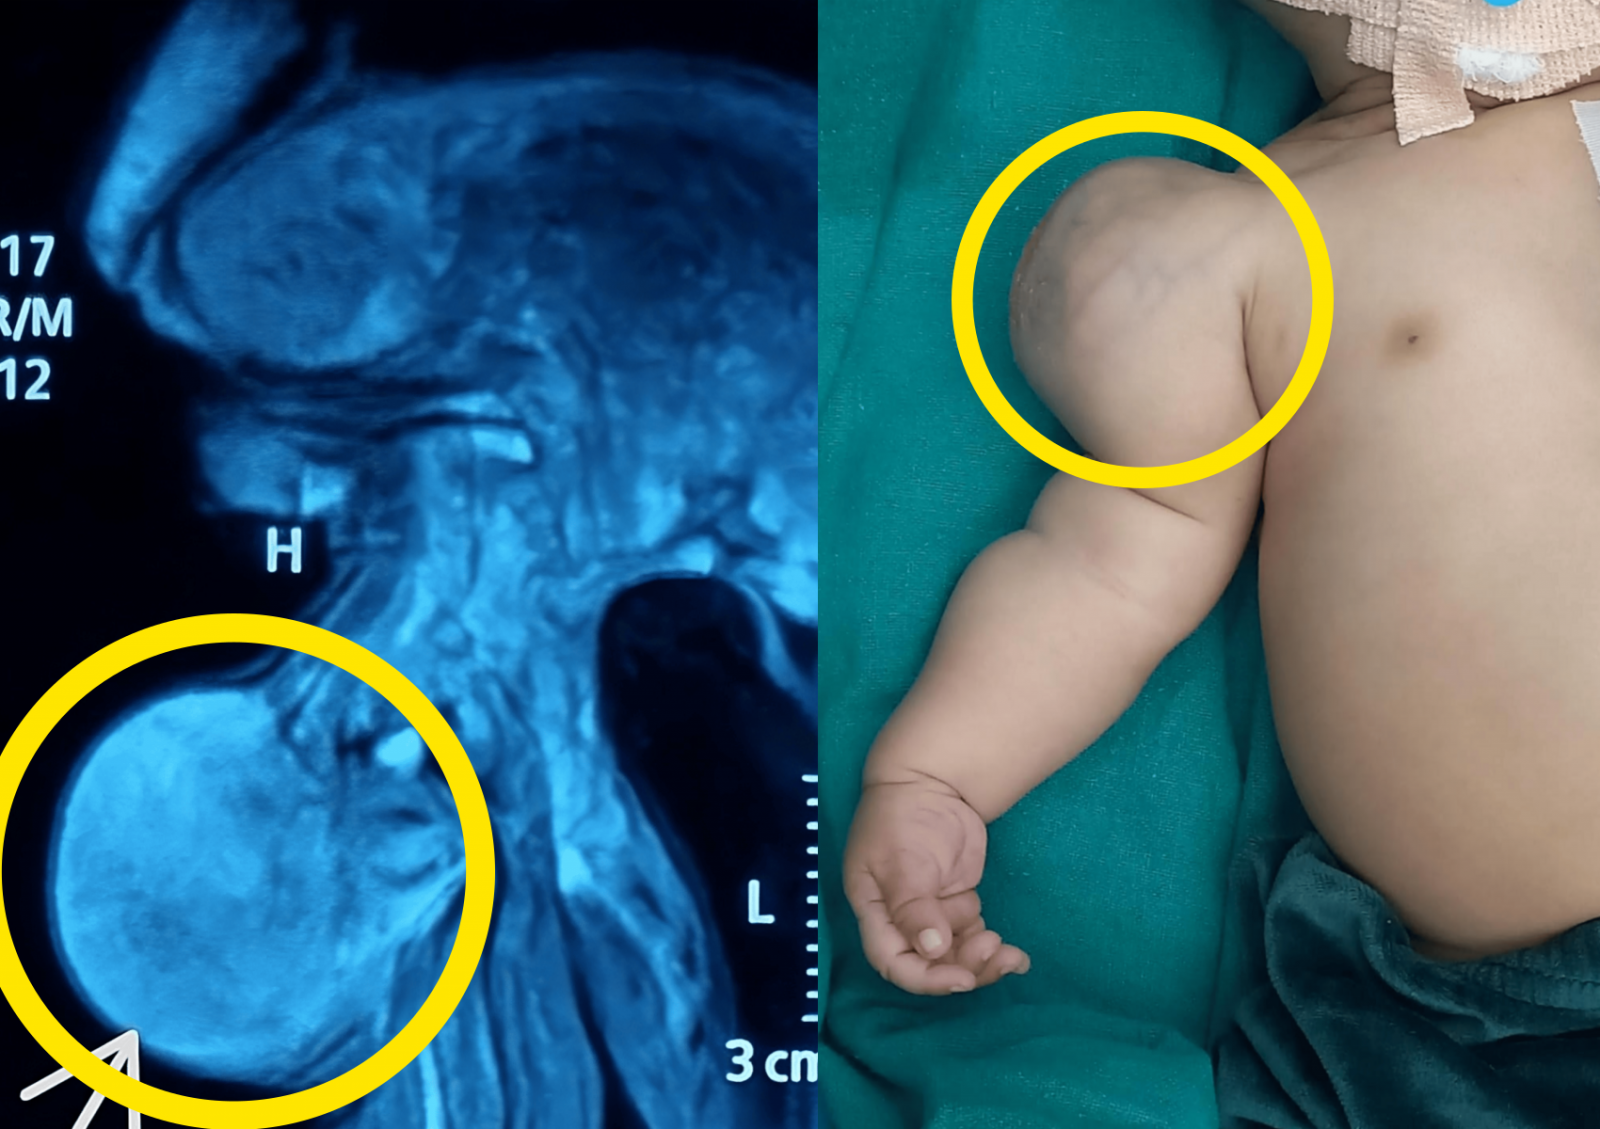

생후 한 달 된 아기의 팔에서 점점 커지는 혹이 발견됐다. 최종 진단은 희귀 악성 종양 저등급 영아 섬유육종이며, 수술 후 아기는 정상적으로 성장하고 있다. (사진=Cureus)생후 한 달 된 아기의 팔에서 점점 커지는 혹이 발견됐고, 최종 진단은 저등급 영아 섬유육종이라는 희귀 악성 종양이었다.

아이는 정상적인 자연분만으로 태어났으며, 출산 주수에도 이상은 없었다. 그러나 출생 직후부터 오른쪽 어깨에 혹이 있었고, 시간이 지나면서 점점 커졌다. 피부 위로 통증은 없었다.

자기공명영상(MRI)에서는 근육 속 연부조직에서 종양이 확인됐고, 뼈 손상은 없었다.

사진=Cureus의료진은 전신마취 하에 국소 절제술로 종양을 제거했다. 제거된 종양은 6.5cm 크기였으며, 종양 위로 또 다른 피부 막이 감싸고 있었다.

최종 조직검사 결과는 저등급 영아 섬유육종으로 나타났다. 이는 1세 미만에서 발생하는 연부조직 육종 중 가장 흔한 유형이다.

사진=Cureus병원은 수술 후 1년간 아기를 추적 관찰했으나 재발이나 팔 기능 장애는 보고되지 않았다. 현재 아기는 정상적인 피부 상태를 유지하며 성장 중이다.